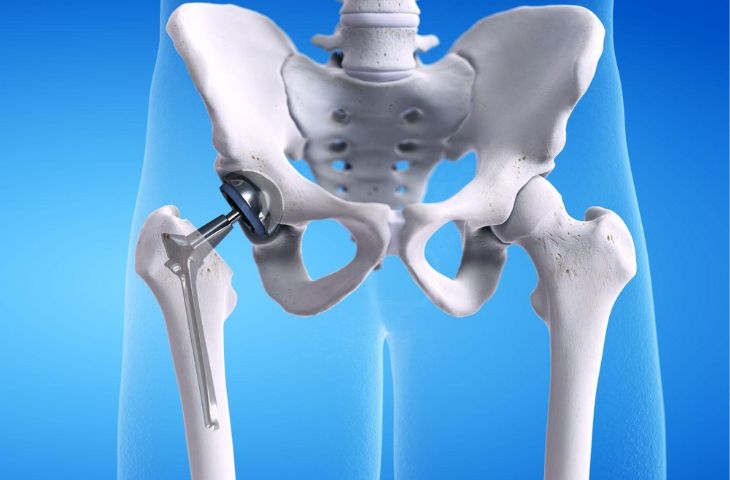

- Thay khớp háng toàn phần: được chỉ định cho bệnh nhân bị hoại tử chỏm xương đùi, gãy cổ xương đùi không có khả năng bảo tồn, thoái hóa khớp háng nặng không đi được, bệnh lý vùng cổ xương đùi như bướu… Thay khớp háng toàn phần được thực hiện bằng cách ghép khớp nhân tạo có chức năng tương tự khớp tự nhiên vào cơ thể.

Phẫu thuật thay khớp háng

Sau phẫu thuật thay háng bệnh nhân có thể gặp một số biến chứng như nhiễm khuẩn, hình thành cục máu đông, máu tụ trong khớp, cứng khớp, mòn khớp, lỏng khớp nhân tạo, di lệch ổ khớp… Chính vì vậy, việc lựa chọn địa chỉ phẫu thuật uy tín với đội ngũ bác sĩ giỏi chuyên môn, máy móc hiện đại, phòng mổ đạt tiêu chuẩn chính là các yếu tố quan trọng hàng đầu để giảm thiểu tối đa các biến chứng hậu phẫu.